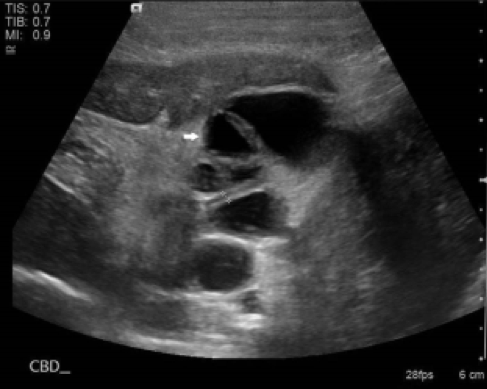

嗜中球性和淋巴球性膽管炎在超音波影像上並沒有明顯的差別。超音波影像下可能會看到增厚的膽囊壁 (> 1 mm)、總膽管扭曲擴張 (>4 mm)、膽囊內有高回音物質沉積、肝臟回音性增高及肝腫大等異常 (圖1)。值得注意的是,並非所有膽管炎都會呈現影像上的異常。狗的膽泥沉積很常是不具臨床意義的,但在貓若看到膽泥沉積的影像,就必須懷疑可能有膽囊炎或其它任何會造成膽泥排出異常的疾病。

圖1、這隻患有膽管炎的貓在超音波下可見總膽管明顯擴張且扭曲 (白色箭頭)、膽囊壁增厚,且膽道內有一些高回音物質。